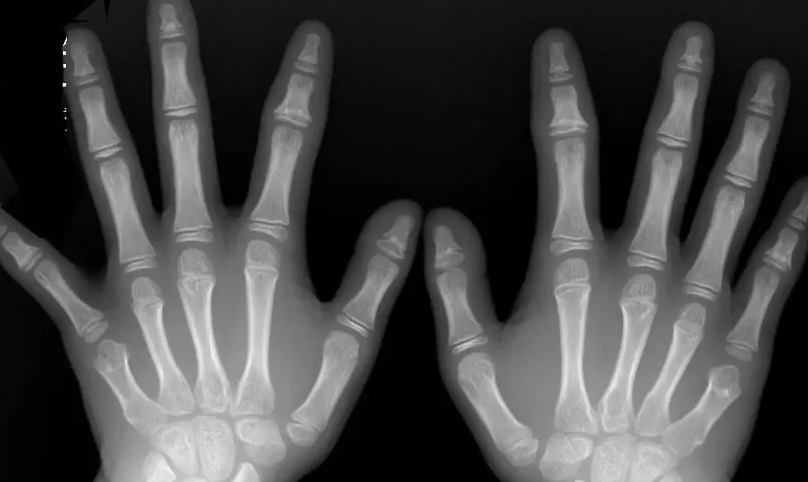

家长们忧虑小朋友身高的时候,一般都会带着孩子去医院做骨龄检测。由骨骺开始,小朋友的骨骼慢慢生长,生长到后期,身高的增长会趋于停止,这是因为骨骺线慢慢闭合了。

骨骺与干骺线之间,有一个软骨,这就是骨骺线。它是骨两端的软骨在生长发育的过程中呈现出来的骨化点,从X光片上看,它是一条宽宽的透光带。不同于其他不会骨化的软骨,像耳软骨、鼻软骨这些,骨骺线是跟着人体的生长一起逐渐骨化的。换句话说,骨骺线通过逐步的骨化,来延长长在四肢软骨上的时间,帮助身高去长高。

在年龄上升的过程中,骨骺线慢慢的变短了,直到它和干骺端的软骨彻底骨化,从一条线变成一条缝,这时候就代表着骨骼不再生长了,骨骺线彻底闭合了。通过骨骺线软骨细胞不断地进行增殖和骨化,小朋友的身高得以长高。时间推移过程中,性激素也在分泌,在青春期发育过了些时间后,原本存在固有程序性变化的骨骺线开始有了趋于衰老的变化,包括功能性和组织性两个方面,与此同时,软骨细胞也失去了繁殖和骨化的能力,因此软骨骨化的空间和原料也消耗完了,这个过程便是骨骼线闭合,经过这个过程,身高也就不再增长了。骨骺线闭合的时间并不是固定的,不同的小朋友存在着个体差异性。对于女孩子来说,有些12岁就闭合,有些14-16岁左右,相对早一些;而男孩则晚一点,有些16-18岁,还有的人更晚点。